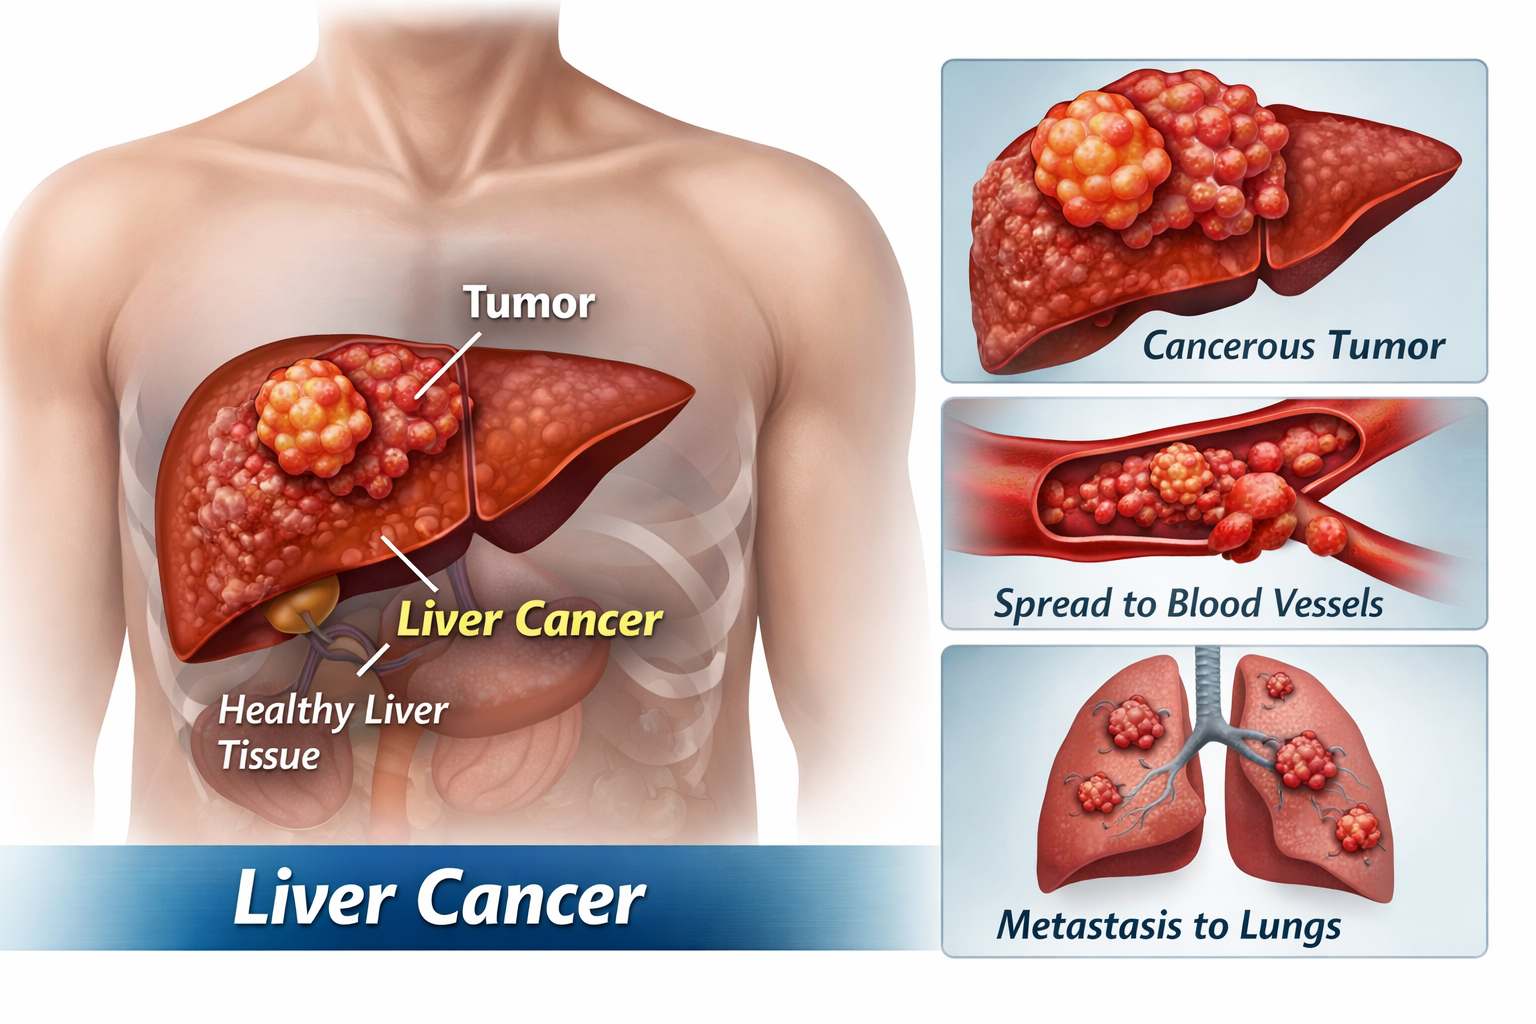

Looking for Hepatitis C treatment in Hyderabad? Dr Rahul Dubbaka offers advanced antiviral therapy with 95%+ cure rates at People’s Hospital, Pragathi Nagar. Book your consultation today at +91 9100921514. Hepatitis C is a viral infection that primarily affects the liver and can silently damage it over time. If left untreated, it may lead to serious complications such as cirrhosis, liver failure, and even liver cancer. The good news is that with modern medical advancements, Hepatitis C is now highly curable with effective antiviral medications.

Over time, chronic Hepatitis C can cause progressive liver inflammation, leading to fibrosis (scarring), cirrhosis, and increased risk of liver cancer.

Complications of Untreated Hepatitis C

If not treated, Hepatitis C may lead to:

Liver cirrhosis

Liver failure

Portal hypertension

Ascites

Liver cancer (Hepatocellular carcinoma)

Early treatment prevents these complications and improves life expectancy.